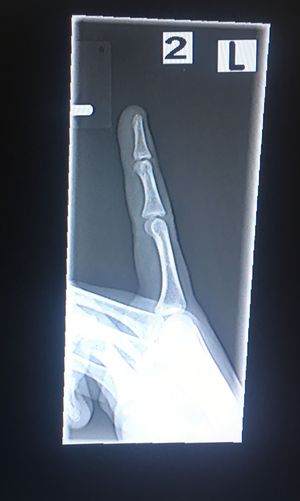

A scan from the side

That is the same finger from the last picture that I posted. What’s the diagnose?

Finger

Broken Bone